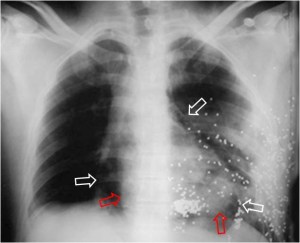

SIGNO DEL CORAZÓN PEQUEÑO

Signo de neumopericardio a tensión en la radiografía posteroanterior o anteroposterior de tórax. El neumopericardio es un hallazgo infrecuente que puede ocurrir en pacientes con traumatismo torácico. El signo del corazón pequeño consiste en una disminución del tamaño de la silueta cardiaca (como consecuencia del aumento de presión en el espacio pericárdico) y se acompaña de signos hemodinámicos de taponamiento cardíaco.

En la imagen, un caso de neumopericardio en un cadáver. Las radiodensidades puntiformes del hemitórax izquierdo corresponde a múltiples perdigones . Las flechas blancas marcan el contorno pericárdico y las rojas el cardiaco. Entre ambas, la zona radiolucente corresponde al neumopericardio.